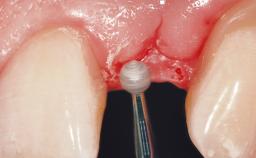

Early Placement of an Implant in a Maxillary Right Central Incisor Site

This 41-year-old female patient was referred to the clinic for the replacement of the right central incisor, since the tooth had developed a root fracture in the long axis that made extraction necessary. The healthy, non-smoking patient was first seen with the tooth still in place. A detailed Esthetic Risk Assessment was performed.The patient was worried about her dental esthetics and had high expectations for a successful treatment outcome from an esthetic point of view. The patient had a medium lip line that displayed parts of the gingiva in the anterior maxilla upon smile.